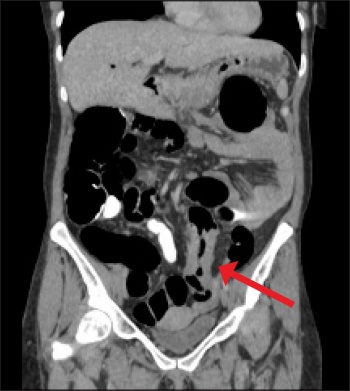

If colonoscopy is incomplete or unsuccessful in patients who have a positive faecal immunochemical test, computed tomography (CT) colonography will be available as the completion examination through the NCSS colorectal screening programme.3,4 This investigation is also indicated in patients who are medically unfit for colonoscopy. CT colonography offers a minimally invasive examination of the colon to evaluate for colorectal polyps and neoplasm. This examination should be performed and reported by a consultant radiologist with specific training in the technique (see Figure 1).

Figure 1. CT colonography (coronal reformat) demonstrating circumferential mural thickening of the sigmoid colon consistent with a sigmoid malignancy

Figure 1. CT colonography (coronal reformat) demonstrating circumferential mural thickening of the sigmoid colon consistent with a sigmoid malignancy(click to enlarge)